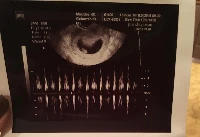

Terhesnapló10 - Liza: Kisfiúnk lesz! (19. hét)

Igazán vártuk már ezt az ultrahangot. Reménykedtünk benne, hogy végre megtudjuk a kis magzatunk nemét, és ezután nem csak krumplibabának hívjuk majd, hanem Barnabásnak vagy Juliannának.